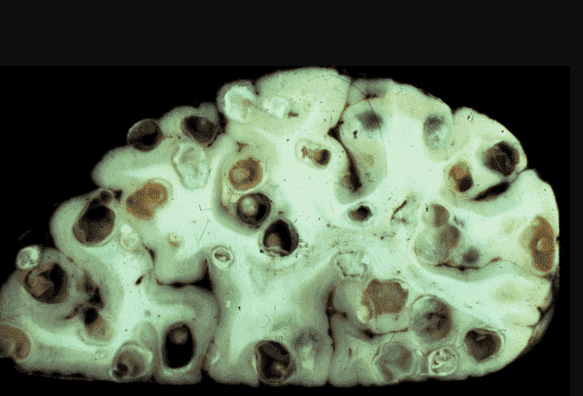

Ένας εγκέφαλος που έχει προσβληθεί από τα παράσιτα

Γιώργος Γαβριηλίδης: Ναι, είναι αλήθεια. Σχεδόν στο 90% των περιπτώσεων, όταν κάνω νεκροτομή, βλέπω μια τρομερή εικόνα. Τα πτώματα είναι γεμάτα με τα παράσιτα! Και τα βλέπω όχι μόνο στον γαστρεντερικό σωλήνα, όπως νομίζουν πολλοί άνθρωποι. Τα παράσιτα ζουν συχνά στους πνεύμονες, στην καρδιά, στο ήπαρ, ακόμη και στον εγκέφαλο! Οι αποικίες τους κατοικούν σε εσωτερικά όργανα και οι προνύμφες τους τρέφονται με τους ιστούς των ζωντανών ανθρώπων!

Μια άλλη περίπτωση: ένας άνδρας 61 ετών. Πέθανε από κίρρωση του ήπατος. Οι συγγενείς του πιστεύουν ότι φταίει το αλκοόλ. Όμως δεν έπινε τόσο πολύ και δεν υπήρχαν ίχνη αλκοολικής καταστροφής του ήπατος, αλλά το ήπαρ απλά έφαγαν από μέσα τα παράσιτα, και βρήκα εκατοντάδες περάσματα μέσα από τα οποία ταξίδευαν τα σκουλήκια.

Άλλη μια περίπτωση που με σόκαρε. Ο εγκέφαλος ενός 49χρονου ασθενούς ήταν γεμάτος με παράσιτα και τις προνύμφες τους. Η αιτία θανάτου ήταν ένα ισχαιμικό εγκεφαλικό επεισόδιο. Αλλά αυτή ήταν μόνο μία από τις συνέπειες! Στην πραγματικότητα, τα παράσιτα απλώς τρέφονταν με τον ανθρώπινο εγκεφαλικό ιστό, τρώγοντάς τον ζωντανό! Καθ' όλη τη διάρκεια της ζωής του, ο ασθενής υπέφερε από πονοκεφάλους, προβλήματα ύπνου και μνήμης. Στη συνέχεια, με πολλές περιοχές ήδη προσβεβλημένες, προστέθηκε και η επιληψία. Έξι μήνες αργότερα, πέθανε.